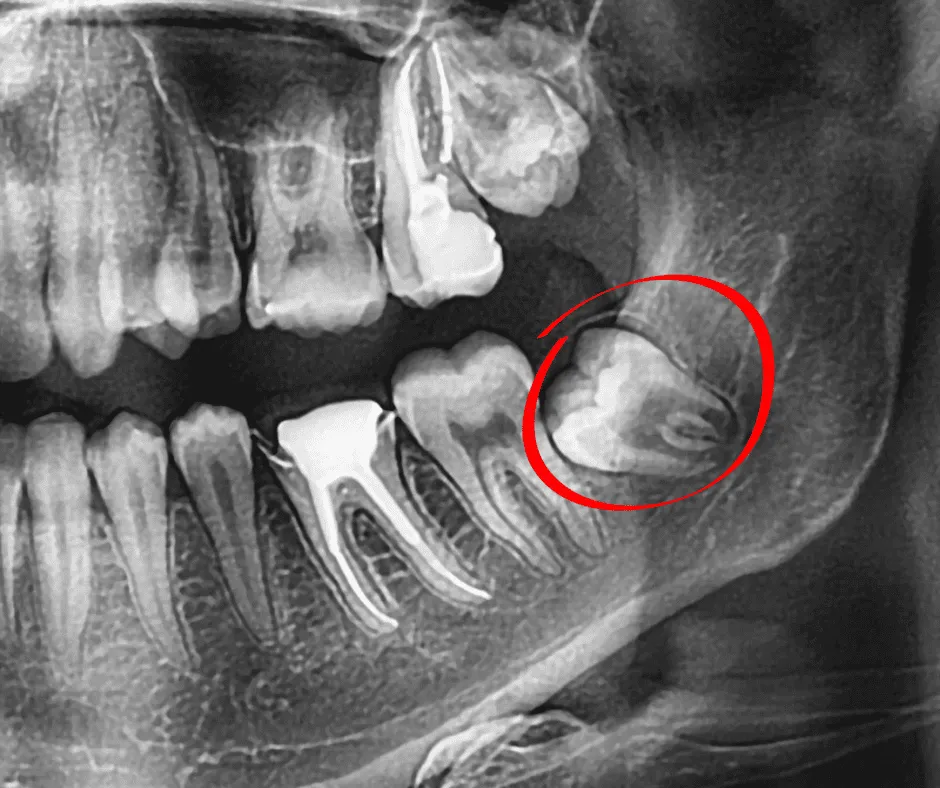

Nuestro equipo especializado cuenta con amplia experiencia en todo tipo de extracciones dentales, desde casos simples hasta complejos como muelas del juicio impactadas, brindando un manejo integral del proceso quirúrgico.

Extracciones

Extracción de muelas del juicio y otras piezas dentales.